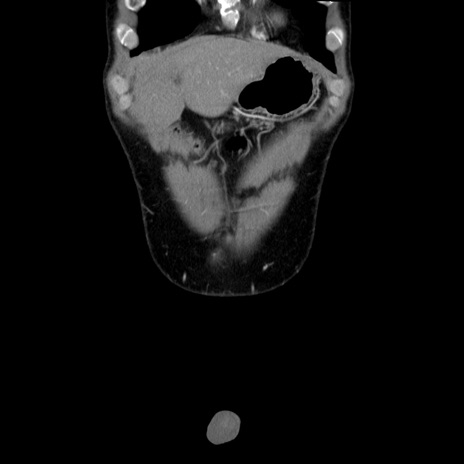

症例36(冠状断像)

【症例】20歳代 男性

【主訴】心窩部痛

【現病歴】今朝より上腹部痛あり。一旦軽快していたが再度出現したため救急要請。昨日夕に白身の魚を含む刺身を食べた。

【身体所見】BP 136/89mmHg、HR 74/min、BT 37.0℃、腹部:膨満、軟、心窩部に圧痛あり。反跳痛なし、筋性防御なし、腸雑音やや亢進あり。

【データ】WBC 17700、CRP 0.48